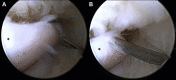

Figure 2

Arthroscopic view of the medial compartment via a direct posterior portal in a right-sided elbow after an attempt to pin the ulnar nerve at the medial gutter (A) and the posteromedial compartment (B) using a needle from the outside-in. The asterisk () marks the tip of the olecranon